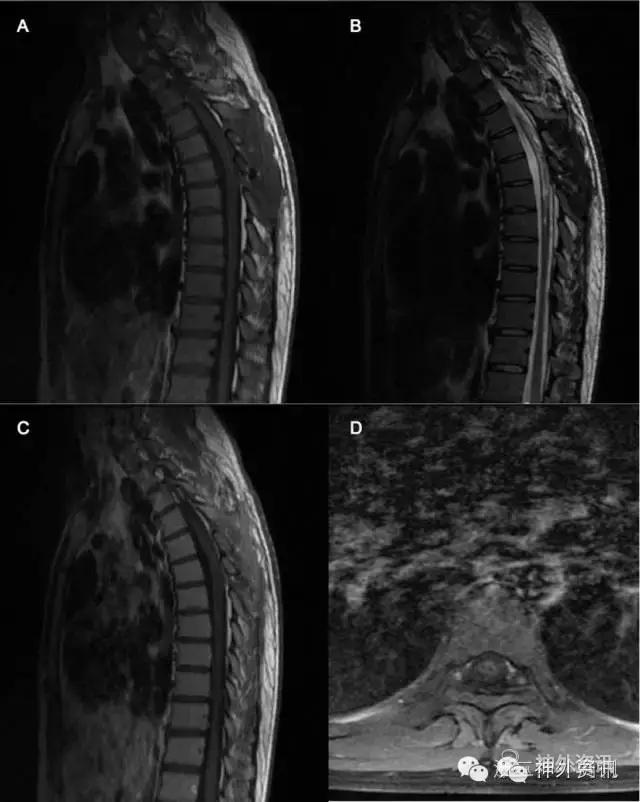

入院后胸椎增强磁共振提示:胸4-5椎间水平髓内占位,大小约13.5 x10.2x10.6mm。病变呈类圆形,边界欠清,位于脊髓内靠后束。周边明显水肿,脊髓中央管扩张,呈脊髓空洞症(图1)。经术前准备,全麻下行胸4-5椎管内肿瘤切除术,术中见肿瘤位于髓内背侧偏左,呈黄白色,血供一般,质地稍韧,有散在钙化,呈鱼肉状,肿瘤背侧边界不清,腹侧面有相对清晰界限,瘤周脊髓可见黄色胶质增生带,沿黄色胶质增生带剥离肿瘤,分块切除肿瘤,达显微镜下全切,不排除背侧紧贴软脊膜处少许残留可能。

图1. A、B:T1像呈低信号,T2像呈混杂高信号;C、D、E:病灶强化明显。